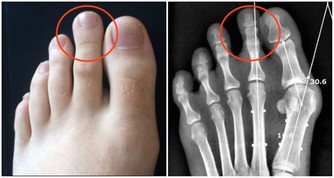

4. 黑頭粉刺、白頭粉刺

通常黑頭粉刺擠出來後粉刺頭是黑色的,粉刺頭下是黃色的硬顆粒。

白頭粉刺可擠出一條條色白細軟的東西。

這兩類粉刺成熟之後一定要清理乾淨,否則會一直積於皮膚之內,撐大毛孔。

而且黑頭粉刺若不擠掉堵在皮膚下太久,易形成褐色或黑色的痣。